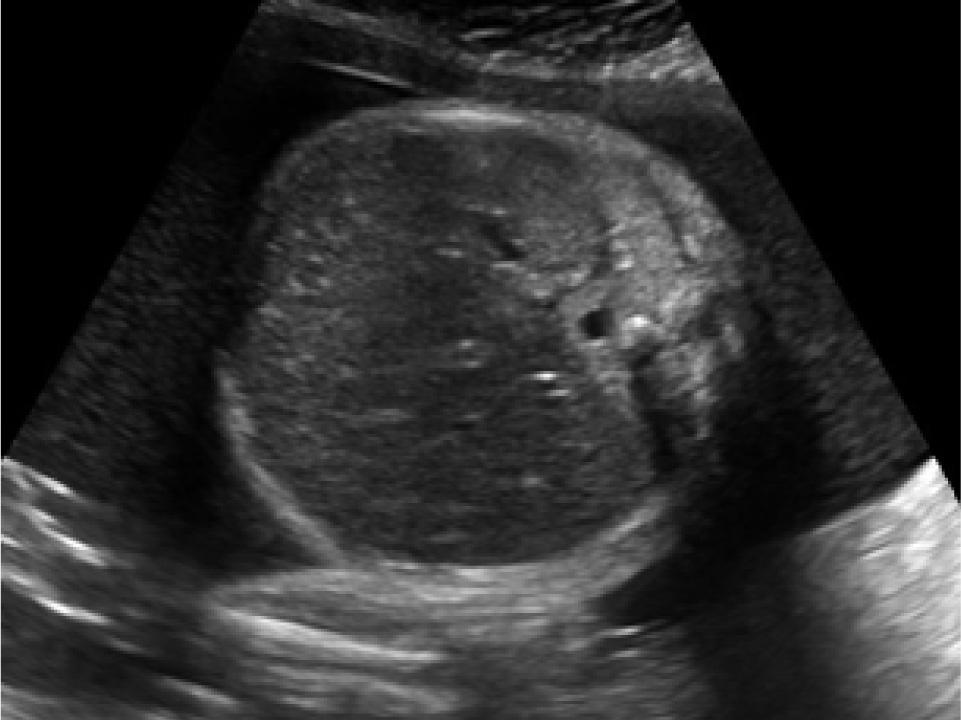

Ultrasonography at 31+1 weeks of gestation revealed severe bilateral ventriculomegaly with areas of hyperechogenicities in the periventricular region (Figure 1), cardiomegaly, hepatosplenomegaly with intrahepatic hyperechogenicites (Figure 2), and polyhydramnios. Fetal congenital infection was suspected and fetal blood sampling was performed and sent for serologic testing. The result was positive for T. gondii IgG and IgM antibodies.

Figure 2

Ultrasound image. Cross-sectional view of the fetal abdomen shows liver enlargement with diffuse intrahepatic calcifications